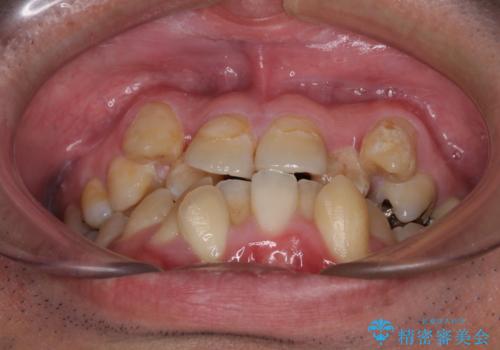

- 上下の八重歯やデコボコを気にして来院された患者様です。

上下ともに八重歯が顕著であったので、上下左右第一小臼歯4本を抜歯し、ワイヤー装置にて矯正治療を行うこととしました。

デコボコが強いことが原因で歯間部に汚れが溜まりやすい状態でしたが、矯正前にできる限り汚れが少なくなるようにブラッシングなどの指導を行い、口腔状態が改善された後にワイヤー装置を装着することとしました。